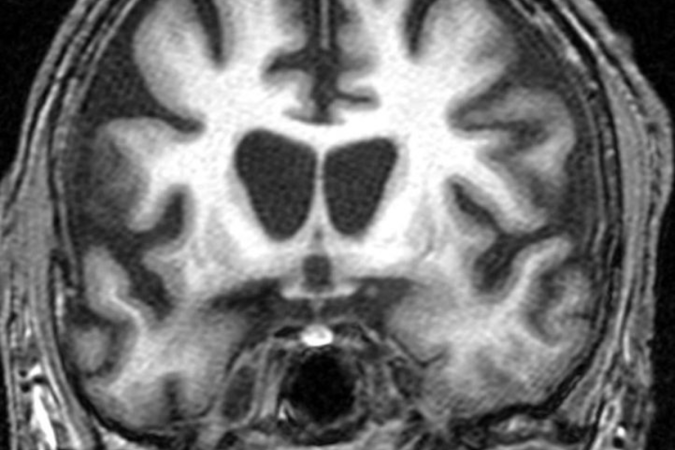

Despite the best efforts of modern medicine, Huntington’s disease is a condition that still comes with a tragic prognosis. Primarily an inherited disease, its main symptoms concern degeneration of the brain, leading to issues with motor control, mood disturbance, with continued degradation eventually proving fatal.